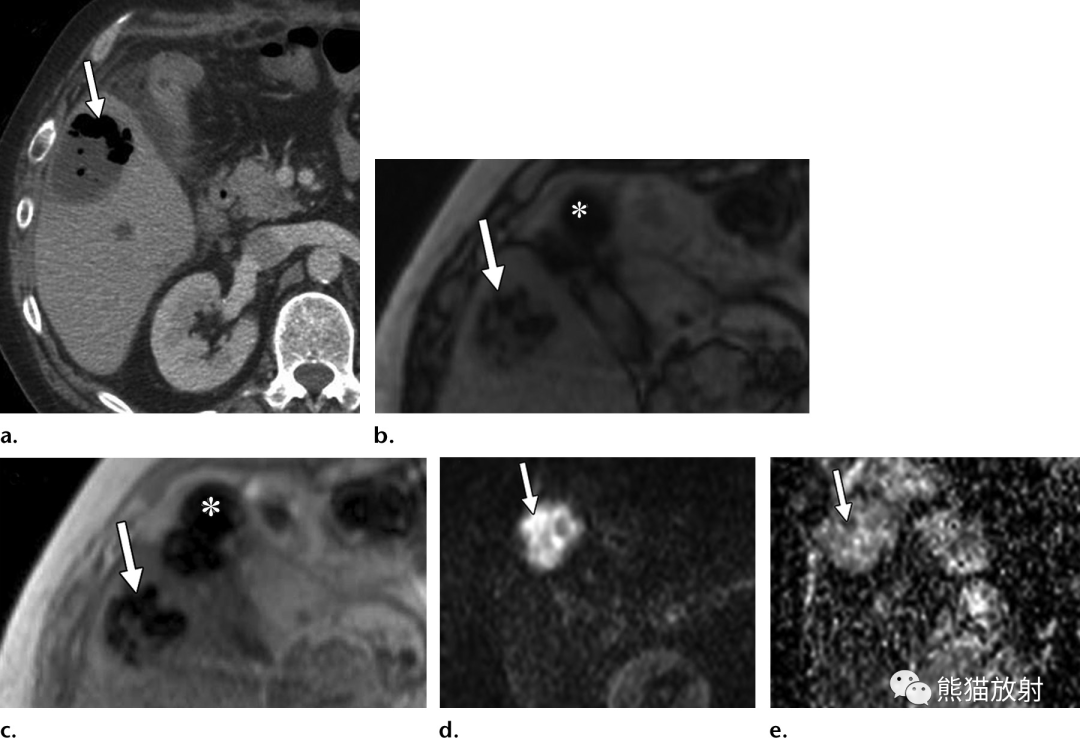

图片

60岁男性,肝片吸虫病,入院前3个月出现发热、盗汗,有西洋菜摄入史。(a)T1WI图像显示肝左外叶和肝右后叶包膜下区域内存在边界不清的小片状低信号(箭)。(b)对比增强动脉期脂肪抑制T1WI显示带状分布的炎症(箭)和周围肝实质的早期强化。(c)增强延迟期图像显示造影剂滞留在寄生的带状肝实质中(箭)。(d)扩散加权图像 (b=800s/mm2) 显示肝包膜下不规则管道样、片状扩散受限区,向肝门中心走行(箭)。(e)冠状T2WI显示胆管远端(箭头)不规则线样低信号充盈缺损,内镜检查结果证实为活的寄生虫。